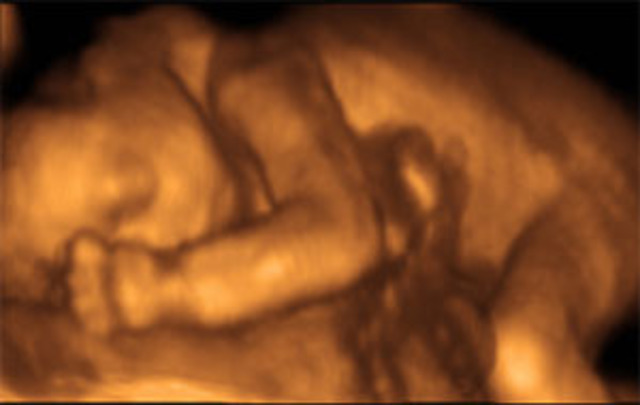

• week 18

week 18

Baby is about 12cm long from crown to rump and weighs about 190grams. Chest moves up and down to mimic breathing. Blood vessels are visible through the babys own skin. Ears are in their final position, although they're still standing out from the head a bit.